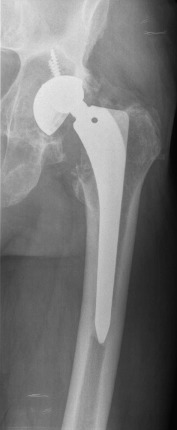

In September 2011 (ten years after primary THA), the patient came to our clinic complaining of hip pain. An important cup asymmetry that indicated wearing of the polyethylene was observed in the radiographic study (Fig. 1 ). The patient was 185 cm tall and weighed 110 kg (body mass index [BMI], 32.14 kg/m2 ). The patient underwent revision of the acetabular component and an exchange of the polyethylene component. Significant metallosis and loosening of the acetabular component was observed. The selected components for the revision were a 58 mm Trilogy® (Zimmer, Winterthur, Switzerland) acetabular shell attached with three (20, 30 and 35 mm) screws with a Trilogy® 58/36 cup. The Bicontact® stem was stable, thus no femoral stem revision was performed. This stem system was an uncemented titanium coated stem with a metaphyseal support. A correct fixation without any sign of collapse and anteversion were evaluated previously to the decision of maintaining the component. A Bioball® (Merete Medical, Berlín, Germany) with a 4XL neck was required to maintain the correct stability of the prosthesis due to laxity with pivoting and external rotation. The Bioball® system consists of different modular neck adapters which allow the surgeon to correct the length and offset of the neck when required. There are eight different sizes between “S” and “5XL” in ascending order, depending on the gap to correct. This implant could be useful specially in those revisions of either stem or acetabular component. Regarding to the case, the most probable cause of this laxity is the placement of the revision cup which is in a high, neutral and horizontal position (Fig. 2 ). The patient had a normal and uneventful postoperative period and remained asymptomatic for two years. He had a Merlé d’Aubigné Postel of 6.6.6 and a Harris Score of 94/100 at the last control.

Fig. 2. Postoperative radiograph after first revision. A Bioball 4XL was required. |